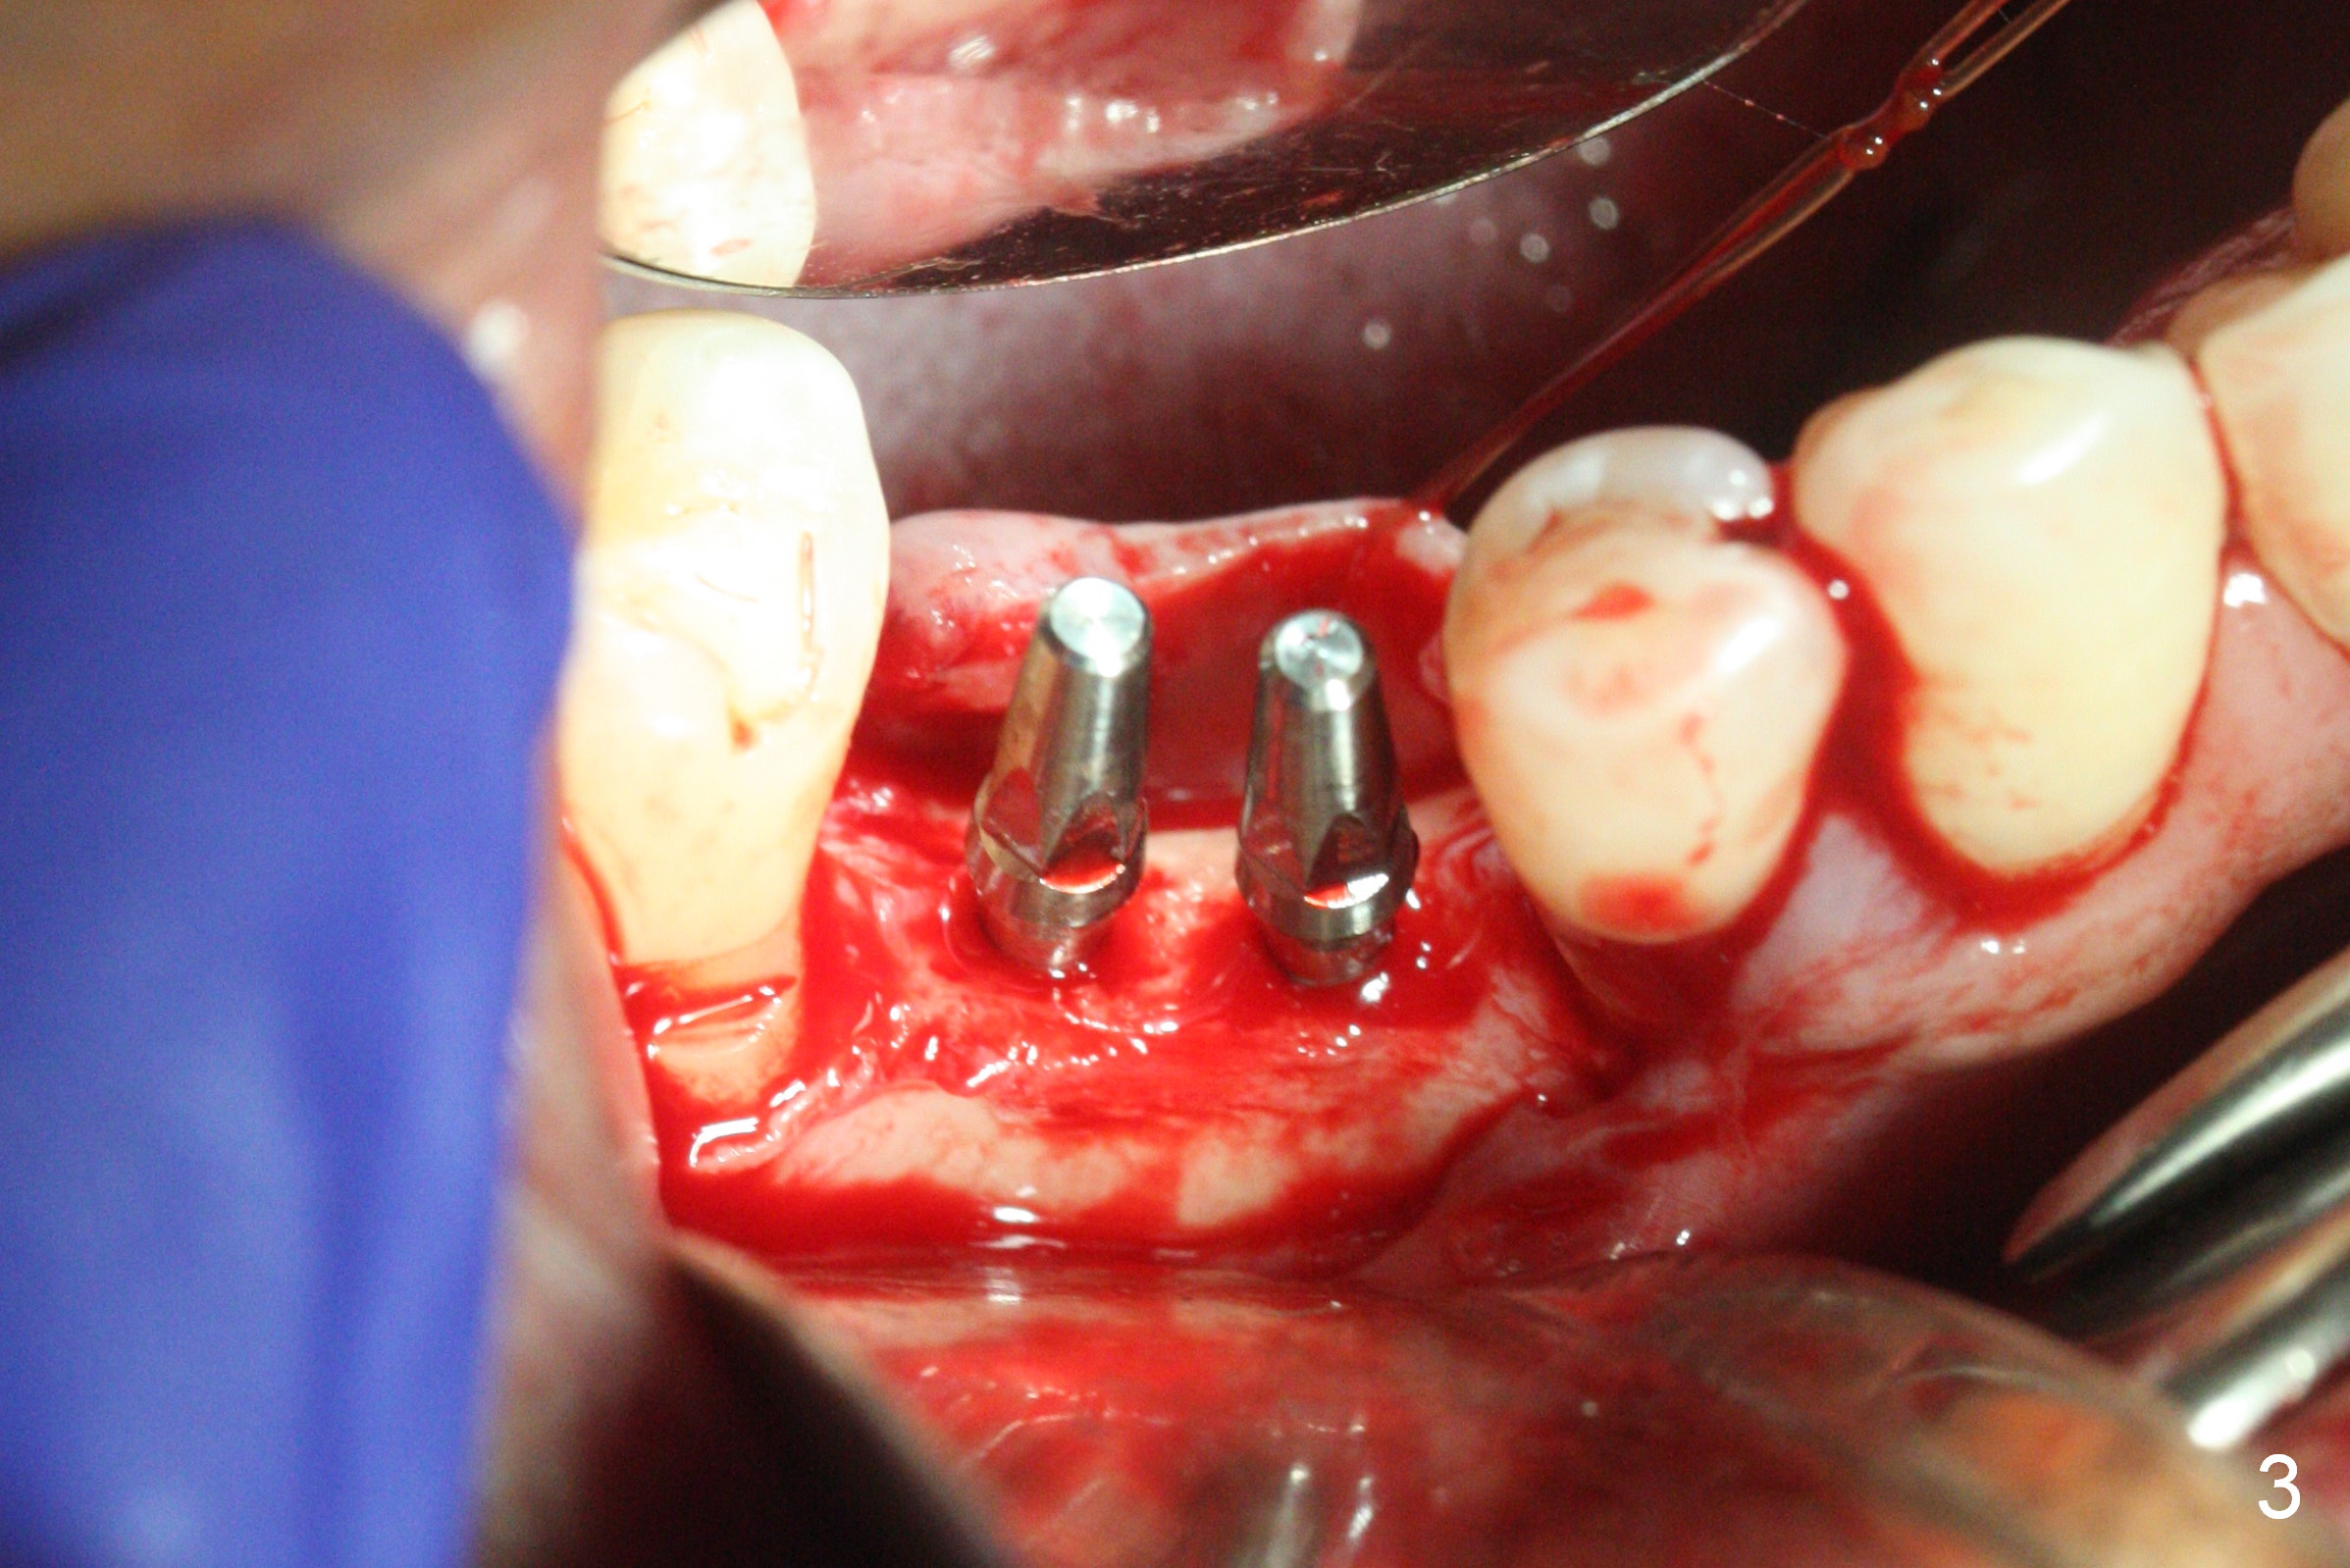

The wide mesiodistal space at #29 is most likely due to congenital missing permanent tooth (i.e., deciduous molar retention before extraction 34 years ago). The patient is now 62 years old. In fact the buccolingual width is not so narrow (Fig.1). After incision, the ridge is approximately 5 mm. Two osteotomies are established with 1.2 mm drill at 8 mm mesially and 1.5 mm one at 10 mm distally (Fig.2). The apparent approximation of the mesial osteotomy to the Mental Loop (red dashed line) is related to X-ray angulation, since there is 1-2 mm separation when two of 2x10(2) mm 1-piece implants are placed (Fig.3,4). Insertion torques of the mesial and distal implants are less than 25 and 15 Ncm, respectively. In fact bone graft is placed around the distolingual root of the tooth #30 after calculus removal (Fig.4 <). Following reduction of the abutments, periodontal dressing is applied locally. The dressing dislodged 13 days postop (Fig.5). A provisional is going to be fabricated 4 weeks postop when the wound heals (Fig.6). No bone loss is observed 4 months postop (Fig.7).